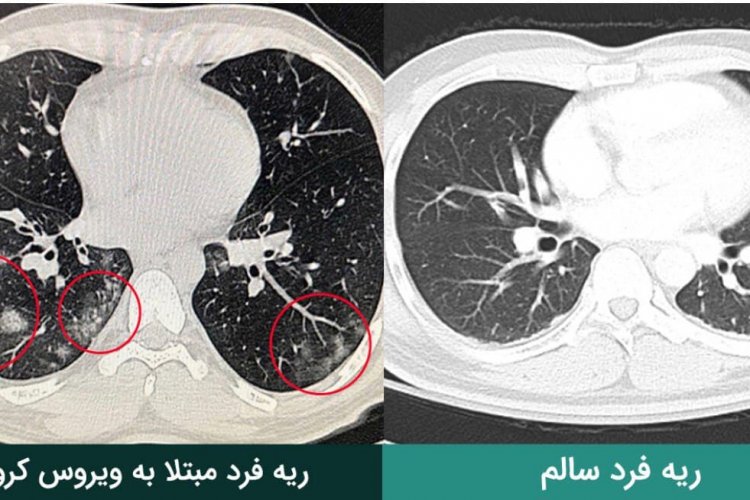

در این فرد ما احتمال پیشرفت بیماری و احتمال درگیری ریه را میدهیم یا فردی که علائم تنگی نفس یا سرفههای پیشرفته دارد. یعنی با وجود همه داروهایی که تجویز میکنیم، نه تنها علائمی مانند سرفه کاهش نیافته، بلکه دارد بیشتر میشود یا کسی که ضعف بسیار شدیدی دارد که برطرف نمیشود و شدت هم مییابد. ما با توجه به این علائم شک میبریم که درگیری ریه داشته باشد و با توجه به این مساله سی تی اسکن ریه میگیریم.

وی گفت: بنابراین سی تی اسکن غیرضروری نباید انجام داد. کسی که روز اول سی تی اکسن انجام دهد، منجر به این میشود که ممکن است یک فرد در سیر بیماریاش دو تا سه بار نیاز به سی تی اسکن پیدا میکند که در آن زمان اشعه زیادی دریافت میکند که برایش خوب نیست و در عین حال شاید تا پایان بیماری هم درگیری ریه پیدا نکند. درگیری ریه در همه بیماران دیده نمیشود، بلکه برخی بیماران درگیری ریه و نیاز به سی تی اسکن پیدا میکنند.

بنابر اعلام وزارت بهداشت، رمضانی گفت: درگیری ریه خفیف هم نگرانی زیادی ندارد، بلکه درگیری ریوی شدید است که باعث میشود درمان و دارو هم تغییر کند.